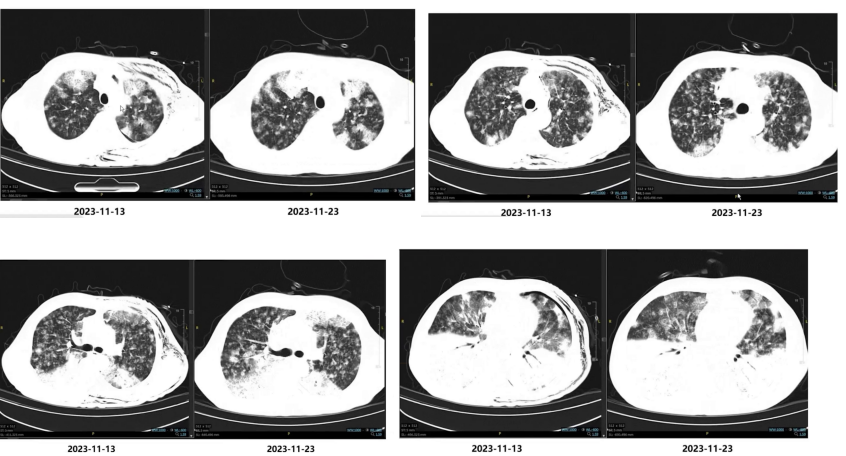

(3)随访影像学变化

再次仔细查体,左侧颈部触摸一个可疑淋巴结,完善浅表淋巴结B超,提示“左侧颈根部颈动脉旁见10mm×7mm低回声团块,未见淋巴门结构,CDFI未见明显彩色血流”。

2023.11.23行超声引导下左锁骨上淋巴结穿刺活检术。

2023.11.27病理:(左锁骨上淋巴结) 穿刺组织于淋巴组织间见腺管状结构,考虑转移性腺癌,部分肿瘤细胞胞浆内含有黏液,参考其临床病史,结合免疫组织化学结果,考虑肺来源黏液腺癌。